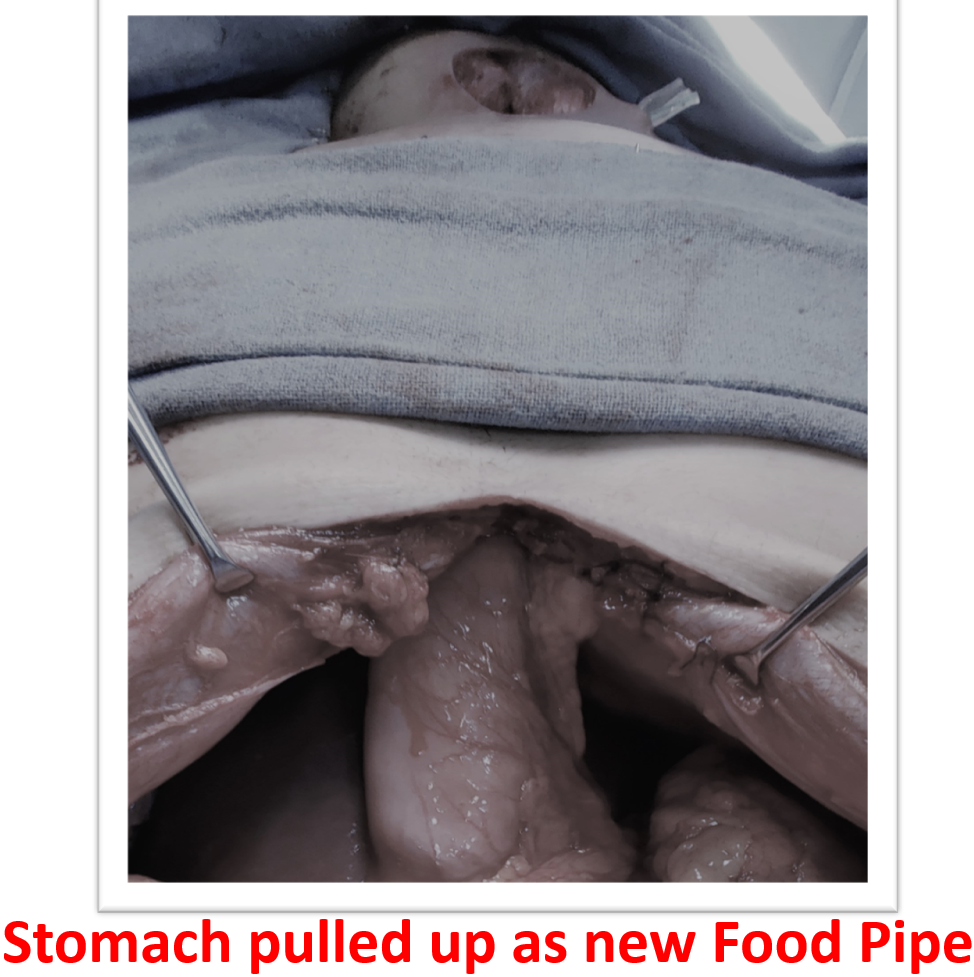

The treatment initially is to dilate the stricture with endoscope to restore eating which might be successful in some. Failing endoscopic dilatation or stricture which has ruptured during dilation need surgical replacement. Surgical replacement has evolved from using artificial pipes to bodies own organs suitable to restore the food pipe. The surgical principle is to identify the healthy upper part of esophagus which is in the neck, leave behind or remove the scarred esophagus, prepare the conduit (stomach tube, colon, jejunum) for replacement, transport it from abdomen to the neck under the chest bone (sternum) and join it to healthy esophagus in neck (Fig- 2/2p/3). The entire procedure involves three major compartments of human body, lasts from 4 to 8 hours, more than a week to recover from surgery and with known procedure related morbidity and mortality if not performed in a specialized centre. Patient are allowed to sip liquids from firs day to resume to normal diet may take a week but eventually they “EAT”